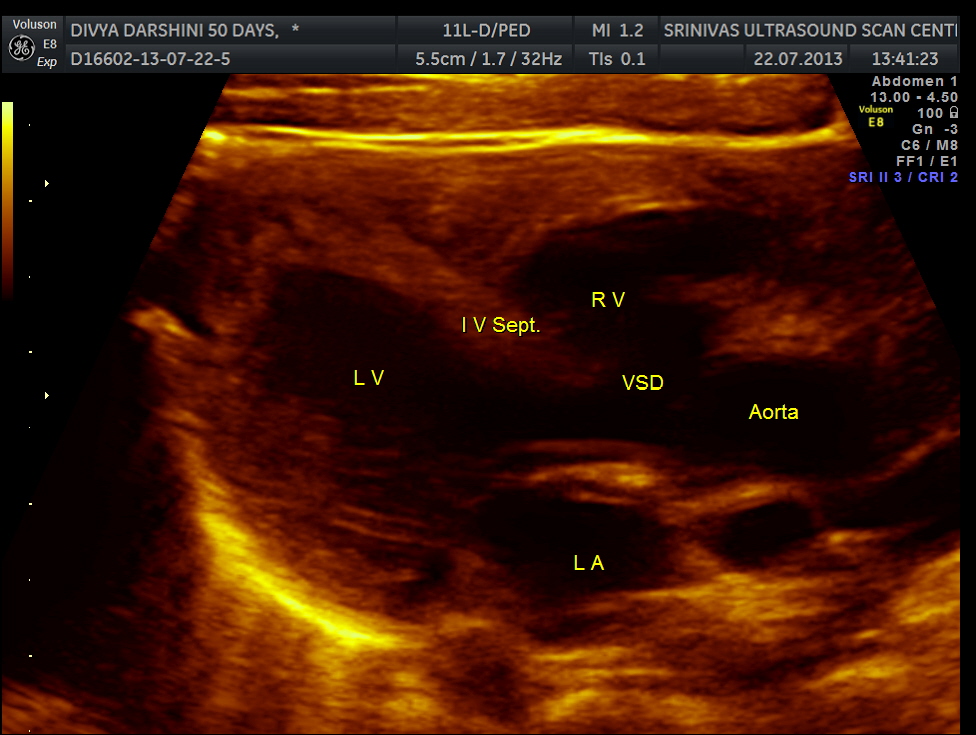

The following pictures are of the heart of the child .

The IVS straddling the aorta is prominently seen ; The RV is mildly dilated . Though the pulmonary artery was difficult to comment on , I would still go with TETRALOGY OF FALLOT with RENAL DYSPLASIA , which makes it complicated.